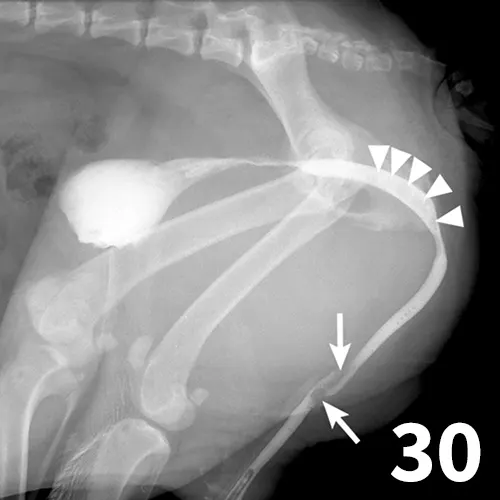

The normal urethra of dogs and cats is difficult to visualize on survey radiography and ultrasonography. Radiopaque urethroliths can be observed on survey radiographs, and therefore the entire urethra should always be included in the field of view (Figure 28). In male dogs, it is useful to pull the hindlimbs forward to assess the urethra between the pelvis and os penis (Figure 29). The prostate gland and proximal urethra, before entering the pelvic canal, can be visualized with ultrasonography, especially if there is urethral distention. In male dogs, the urethra at the proximal os penis can be evaluated with ultrasonography to assess for urethroliths, which commonly lodge in this location. Positive-contrast retrograde urethrography is the best tool for diagnosis of intraluminal, intramural, and extramural compressive urethral disorders as well urethral rupture (Figure 30).

Figure 28.

There are 1 small and 1 large round urethral calculi (arrow) in this cat with urinary obstruction. The bladder is severely distended, and there is decreased detail caudal to the bladder. This demonstrates the importance of including the entire urethra on radiographs when urinary bladder obstruction is present or suspected.